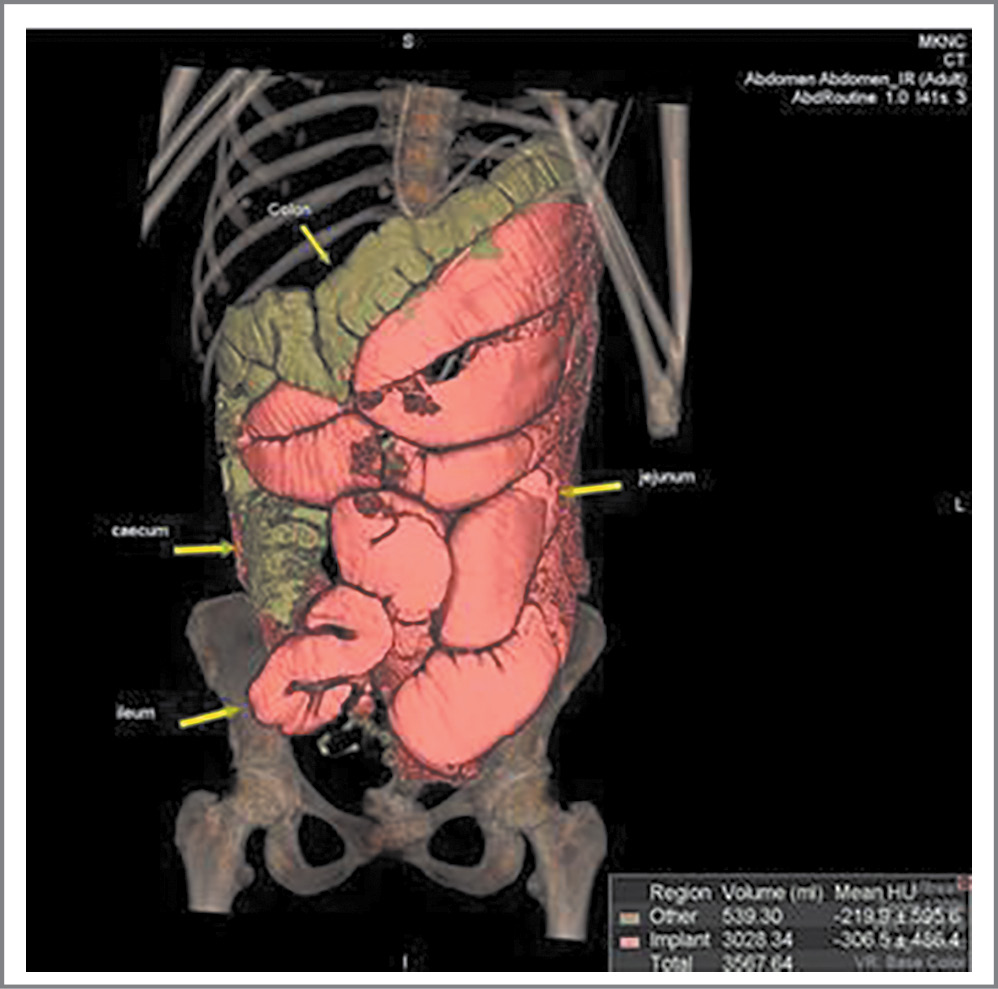

По данным МСКТ брюшной полости выявлены дилатация желудка и двенадцатиперстной кишки, расширение петель тощей и проксимальных отделов подвздошной кишки до 50–60 мм, которые заполнены жидкостью и газом с формированием уровней. Дистальная половина подвздошной кишки диаметром до 20–25 мм (рис. 2).

Рис. 2. МСКТ брюшной полости больной А.

Fig. 2. Multispiral computed tomography of the abdominal cavity of patient A.